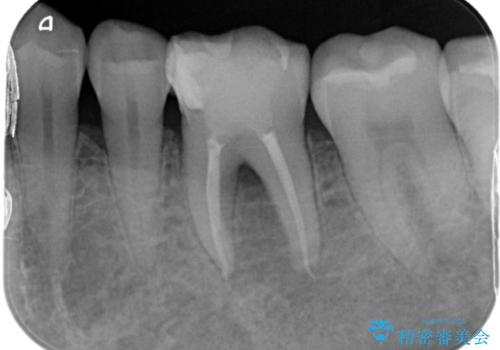

- 1ヶ月前から急に物が当たるだけでも痛いとの事で来院した患者様です。

精密根管治療とオールセラミックで補綴治療を行いました

精密根管治療で痛みはすぐに消退しました。

数ヶ月後には根分岐部の病変もなくなっていました。